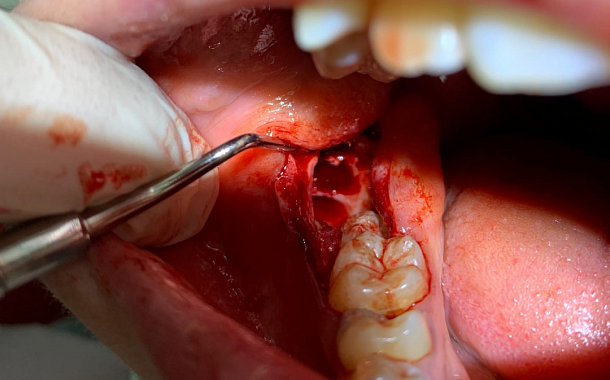

Применение Indiba после стоматологических процедур, таких как удаление зубов, костная пластика и имплантация, обеспечивает ряд значительных преимуществ:

- Ускоренное заживление: за счет стимуляции клеточной активности способствует более быстрому восстановлению тканей.

- Уменьшение отека и боли: улучшение микроциркуляции помогает снизить послеоперационный отек и болевые ощущения.

- Профилактика осложнений: активизация иммунных процессов снижает риск развития инфекций.